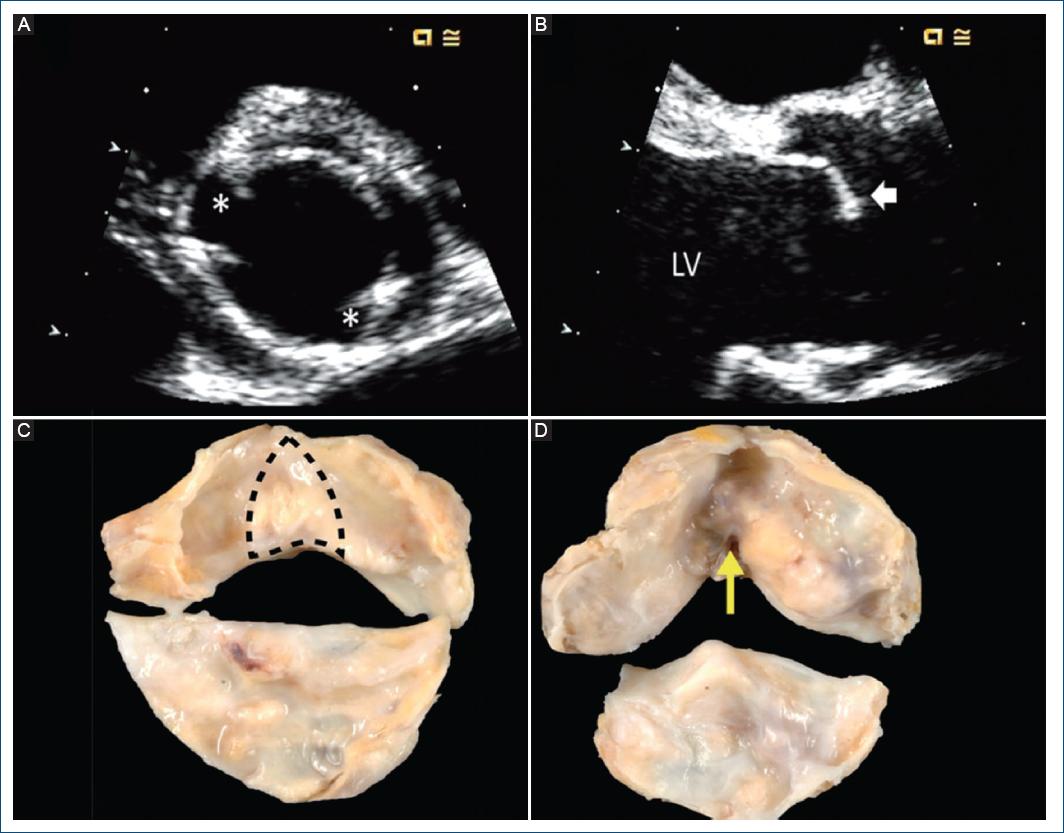

La VAB congénita se diagnostica usualmente con imágenes de la válvula aórtica en el eje corto de la base del corazón con TTE y TC o RMC sincronizada al ECG, demostrando la existencia de solo dos comisuras que delimitan solo dos cúspides valvulares (Fig. 2)2,26. En las imágenes ecocardiográficas de eje longitudinal se puede apreciar una «cúpula sistólica» o domo sistólico en la cúspide fusionada, especialmente en la fusión coronaria derecha-izquierda (Fig. 2), pero este signo es menos confiable para identificar otros fenotipos de VAB. El diagnóstico también se puede hacer mediante observación quirúrgica directa20,27 y mediante un examen patológico28. Es importante reconocer que una válvula aórtica tricúspide que esté calcificada o reumática puede presentar un patrón de fusión adquirida (no congénita) de dos cúspides que puede ser difícil de diferenciar de la VAB congénita; en estos casos, la inspección quirúrgica y/o el examen patológico pueden identificar si la fusión es congénita o adquirida. En quirófano, aunque no siempre es posible, el cirujano puede definir la condición bicúspide congénita comparando la altura de la pseudocomisura (la unión del rafé [pseudocomisura] en la pared aórtica), que es de menor altura dentro de la raíz aortica en comparación con la altura de las comisuras normales, cuya altura de inserción en la raíz es mayor (Fig. 3). Se pueden utilizar características macroscópicas adicionales en la inspección quirúrgica o patológica, como el ángulo formado entre las cúspides fusionadas (obtuso = fusión congénita; agudo = fusión adquirida) y el plano de clivaje en el aspecto ventricular de las cúspides fusionadas (ausente = congénita; presente = adquirida) (Fig. 2).

Figura 2 Diagnóstico de la válvula aórtica bicúspide (VAB) congénita mediante ecocardiografía transtorácica y manifestaciones patológicas. A: imagen sistólica de la válvula aórtica de eje corto paraesternal que demuestra la existencia de solo dos comisuras (asteriscos) que delimitan solo dos cúspides. B: la imagen sistólica de eje paraesternal largo muestra una cúpula sistólica de la cúspide fusionada (flecha), común para la fusión de la cúspide derecha-izquierda. C: la pieza patológica de VAB congénita muestra el área del rafé (línea discontinua) desde la perspectiva ventricular izquierda, formando un ángulo obtuso entre las cúspides fusionadas. D: el lado ventricular de una válvula aórtica tricúspide con fusión reumática adquirida muestra el plano de escisión con ángulo agudo (flecha amarilla). LV: ventrículo izquierdo.